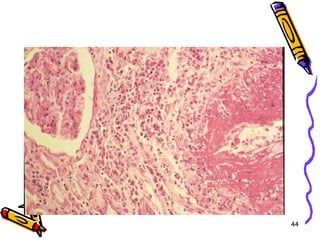

Mikroskopi

• Lezyonlar keskin sınırlı ve segmentaldir

• Fibrinoid nekrozla birlikte lökositik

inflamasyon ve tromboz

• İnflamasyon nedeni ile duvarda zayıflama

ve anevrizmal dilatasyon

• Damarın beslediği dokularda infarktüs,

atrofi, hemoraji